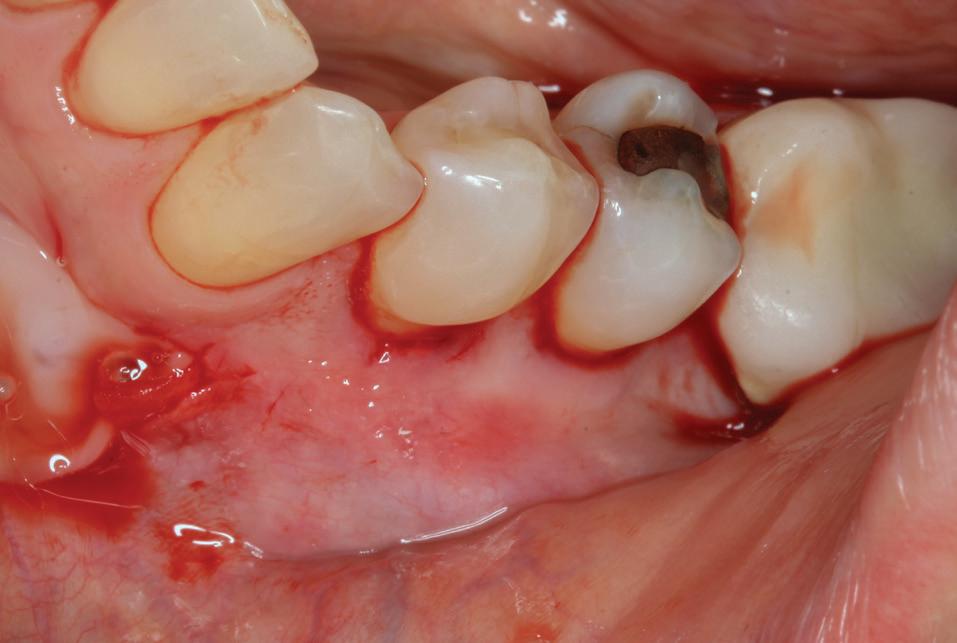

PREZENTARE DE CAZ

Un pacient caucazian în vârstă de 77 ani s-a prezentat la clinica autorului după cinci ani în care nu a fost la niciun control stomatologic. Examinarea clinică a arătat o pierdere semnificativă de os, parodontită cronică și multiple edentații care au destabilizat ocluzia. Pacientul a raportat sensibilitate la rece la nivelul primului molar drept inferior nr. 46, în special la ingerarea de lichide reci. Radiografia periapicală a confirmat constatările examenului clinic; în

plus, s-a detectat și prezența unei carii radiculare la nivelul rădăcinii distale a aceluiași molar, cu răspuns pozitiv la testul de sensibilitate (fig. 1-2).

Planul de tratament a început cu accent pe restabilirea sănătății parodontale. Într-o ședință ulterioară, odată cu îmbunătățirea stării parodonțiului, s-a efectuat restaurarea molarului nr. 46. Sub anestezie la Spina Spix pe partea dreaptă și

Figurile:

1. Situația clinică inițială.

2. Radiografia inițială.

3. Cavitate de clasa a II-a preparată.

4. Septomatrix pe poziție.

5. Cavitatea profundă.

izolarea cu digă de cauciuc, restaurarea din amalgam a fost îndepărtată complet și s-a obținut accesul la cavitatea carioasă (fig. 3-5). În ciuda proximității față de țesutul pulpar, nu a avut loc nicio expunere, iar cavitatea de clasa a II-a a fost restaurată complet cu Biodentine™ (fig. 6-8).